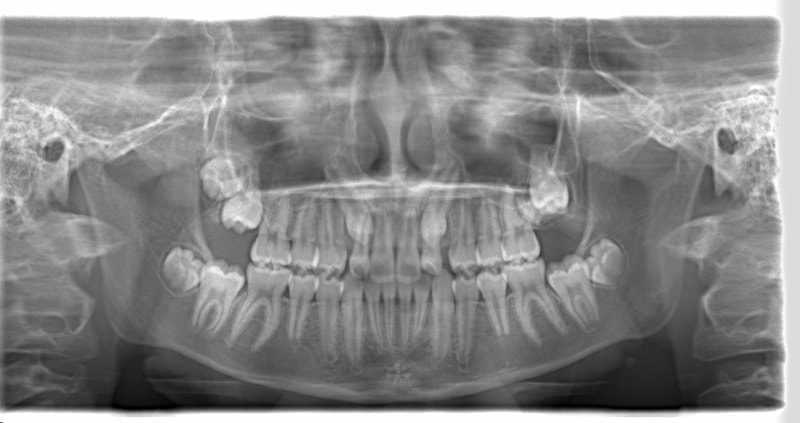

治療法:上顎急速拡大装置+クリアスナップ+フェイスマスク+上顎3番は開窓牽引CT写真にて位置確認

治療前

FX(フェイシャルアキシス)は85度なので東洋人の平均値に近く、下顎が前方に過剰成長するリスクは強くはありません。

しかしやはり上顎は劣成長で、下顎が優位な状態ではあります。

上下顎のギャップはありますが、顔面自体の幅径は良好な値を示していますので、スペース不足は拡大することによって解決できポテンシャルはあると考えられます。

左右の非対称もさほど強くありません。

骨年齢は実年齢よりも低めなので、今後下顎の旺盛な成長が見込まれます。

検査時のレントゲン分析では、上下顎の関係は、上顎の劣成長があり下顎前突傾向という値がでておりましたが、前歯ジャンプ後はフェイスマスクの効果もあり、上下顎の関係は正常化しています。

上顎が若干優位になっていますので、今後の下顎の成長のための貯金になっているくらいです。